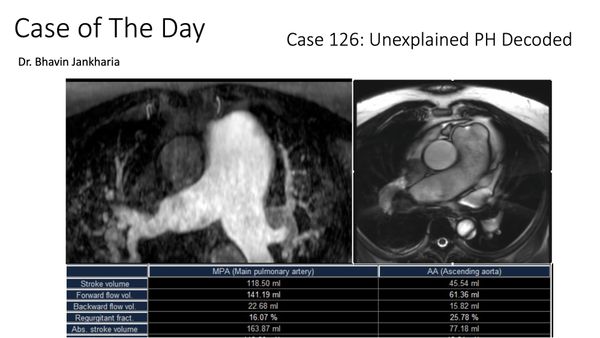

Case of the Day 126 - Unexplained Pulmonary Hypertension Decoded

In patients with PH, radiologists can make a difference in identifying a few pathologies as causes of PH (leaving aside known cardiac and pulmonary diseases, where the conditions are already known). We should not miss these, especially shunts.